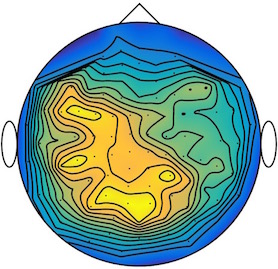

We applied our method to a magnetoencephalography (MEG) dataset. In this setup, brain activity of a subject is recorded (Elekta Neuromag, 306 sensors of which 204 planar gradiometers and 102 magnetometers, sampling frequency 1000Hz) while the subject reacted to the presentation of a target stimulus by pressing either the left or the right button.

Data is preprocessed applying signal space separation correction, interpolation of noisy sensors, and realignment of data into a subject-specific head position (MaxFilter, Elekta Neuromag). The signal was then filtered (low pass 40HZ), and artifacts such as blinks and heartbeats removed thanks to Signal-Space Projection using the Brainstorm software222http://neuroimage.usc.edu/brainstorm. The samples we used for our barycenter computations are an average of the norm of the two gradiometers for each channel from stimulation onto 50ms and the classes were left or right button.

| Class 1 | Class 2 | ||||||

|

|

|

|

|

|

|

|

| Sample 1 | Sample 2 | Sample 3 | Mean | Sample 1 | Sample 2 | Sample 3 | Mean |

|

|

|

|

|

|

|

|

This results in two classes of recordings, one for each pressed button. We aim at computing a representative activity map for each class using Wasserstein barycenters. For each class we have recordings each having samples located on the vertices of an hexahedral mesh of a hemisphere (corresponding to a MEG recording helmet). These recorded values are positive by construction, and we rescale them linearly to impose . Figure 6, top row, shows some samples from this dataset, displayed using interpolated colors as well as iso-level curves. The black dots represent the position of the electrodes on the half-sphere of the helmet, flattened on a 2-D disk.

We computed TV-regularized barycenters independently for each class by solving (16) with the TV regularization using the projected gradient descent method (22). We used a squared Euclidean metric (24) on the flattened hemisphere. Since the data is defined on an irregular graph, instead of (23), we use a graph-based discrete gradient. We denote the graph which connects neighboring electrodes. The gradient operator on the graph is

The total variation on this graph is then obtained by using , the norm, i.e. we use in (23).

Figure 6 compares the naive barycenters (i.e. the usual mean), barycenters obtained without regularization (i.e. ) and barycenters computed with an increasing regularization strength . The input histograms being very noisy, the use of regularization is important to make the area of significant activity emerge from the noise. The use of a TV regularization helps to keep a sharp transition between active and non-active regions.